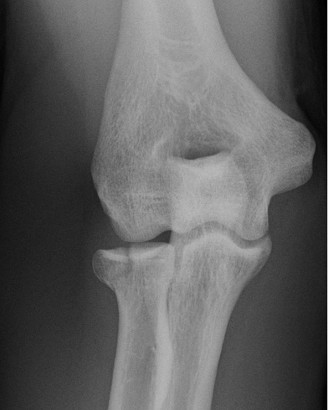

A 42-year-old female presents to the office for follow up after sustaining a minimally displaced radial head fracture 3 months prior. She states she was initially treated in long-arm splint by the ER and did not follow up with an orthopaedic surgeon until now. Per her report, she removed the splint 4 weeks after the injury, but did not move her elbow due to pain. She now has no pain but is unable to reach that hand to her face or head. The remaining history is significant for previous ulnar nerve surgery for which she is unable to provide details. On physical examination, her upper extremity is normal except for limited flexion/extension, measured to be 80 to 50 degrees by goniometer. In addition, she has a well-healed surgical incision about the medial elbow, consistent with a previous surgery on her ulnar nerve. Her images are shown (Figs. 2–82 to 2–84).

Figure 2–83